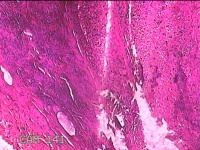

右拇指肿物

性别

女

年龄

23岁

临床诊断

1.右拇指肿物性质待查? 2.腱鞘巨细胞瘤

一般病史

发现右拇指肿块7月余。

标本名称

大体所见

灰白粉红色肿物2x1.5x0.8cm一个,表面光滑,肿物表面有少许脂肪,切开肿物呈实性,切面灰白粉红色,质中。

不具诊断价值。